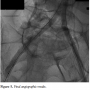

The patient did quite well following his revascularization, which helped facilitate wound healing. However, about 3 weeks later, he developed acute limb ischemia of the right lower extremity so he was brought back to the cardiac catheterization lab. Access was obtained in the right brachial artery using a 6 Fr Destination sheath. Bivalirudin was used for anticoagulation. Angiogram revealed thrombotic occlusion of the right common and external iliac artery stents (Figure 3). As we were not able to cross the lesion with multiple attempts, we decided to